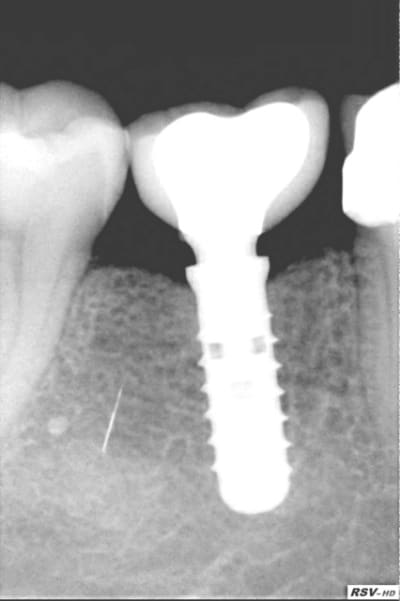

Mais voilà face à autant de certitudes regardez ce que l'on peut obtenir en 1 an seulement.

Allez niez l'évidence! (Dans les memes conditions que notre cher confrere)

Juste une question: Que faut il pour avoir de l'os?

tes radios sont géniales!

même le point de contact a repoussé, bravo!:-))